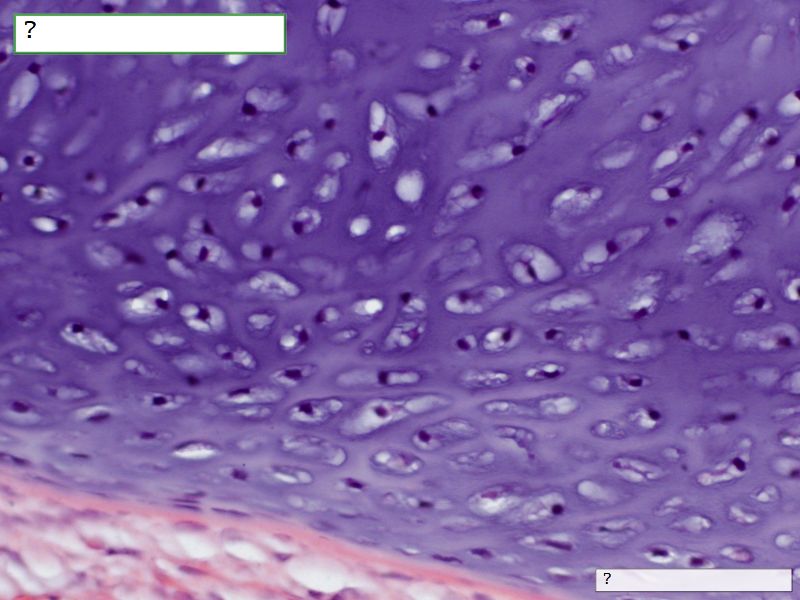

Fill in all the missing labels, and assess as you move through the slides. Answers on the down slide. It is important to do this using pen and paper, and not just glance through the images.